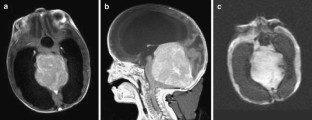

Fig. 3